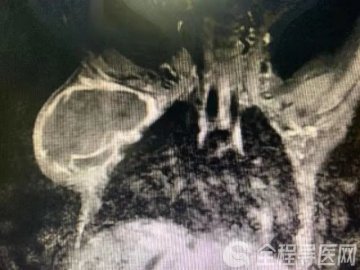

全程导医网 徐州就医信息/徐州儿科频道:10个多月的男宝宝小旭从小就“体质差”,非常容易受凉感冒,而且每次受凉感冒之后就出现“咳嗽、气喘”,还不容易好,每次都得去医院“输液、雾化吸入”才能好,还非常容易反复,治疗几天稍微好一点,隔一夜咳喘又加重了,在当地医院多次住院,都被诊断为“支气管肺炎、支气管哮喘可能”,可把小旭的父母愁坏了,“这可怎么办呀?”“这个病能治好吗?”后来,无奈的小旭爸爸妈妈把小旭带到了徐州市儿童医院的呼吸内科住院治疗,行胸部CT检查发现气管下段狭窄,请我科会诊后考虑血管环形成压迫气管造成气管狭窄的可能性极大,建议行心脏CTA+气管三维重建、纤维支气管镜检查后确诊为“血管环、气管狭窄”,转入心胸外科治疗,继续抗感染、化痰平喘等治疗,完善术前准备后行“血管环矫治术”,手术中缝扎切断血管环韧带和动脉导管韧带后松解血管环,患儿气管及食管受压解除,气管通气时震颤消失,患儿支气管肺炎很快治愈,经一周左右恢复后顺利出院,未再出现咳嗽气喘症状。

所谓的“血管环”是指胎儿发育早期由成对的主动脉组成的血管环未能正常地向单一主动脉过渡,其右背侧主动脉退化吸收不全或主动脉弓其他各段发育异常,使小儿主动脉弓依然保留完全或不完全的环形结构,而行走在血管环内的食管和气管受到不同程度的压迫,这种主动脉弓各段组合方式的异常称为血管环畸形。血管环畸形的发生率在东方国家较低,畸形血管包绕食管和器官,对它们产生压迫,引起临床症状,从而需要外科处理,以缓解症状。